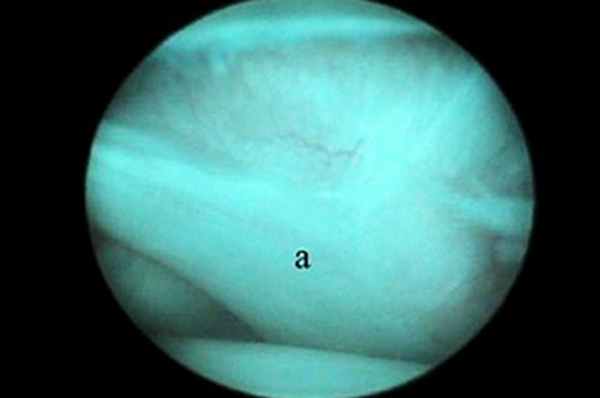

Артроскопия плечевого сустава

Показания к артроскопии плечевого сустава включают РОХ головки бедренной кости, нестабильность сустава, тендосиновит сухожилия двуглавой мышцы плеча, повреждение сухожилия подлопаточной мышцы и переломы хряща. Благодаря артроскопии плечевого сустава стало возможно диагностировать и лечить причины хромоты, сложно поддававшиеся диагностике ранее. Сухожилие двуглавой мышцы (рис. 1), Y-образная медиальная суставно-плечевая связка (МСПС) (рис. 2) и каудальная часть головки плечевой кости хорошо визуализируются.

| Рис. 1. Место прикрепления сухожилия двуглавой мышцы на надсуставном бугорке хорошо визуализируется с помощью артроскопа. Артроскоп можно продвинуть ниже через межбугорковую борозду для оценки состояния сухожилия по его ходу вдоль борозды. Рис. 2. Медиальная суставно-плечевая связка (МСПС) хорошо визуализируется с помощью артроскопа (а). Рис. 3. Каудальная часть головки плечевой кости (а) и суставная впадина лопатки (b). | ||